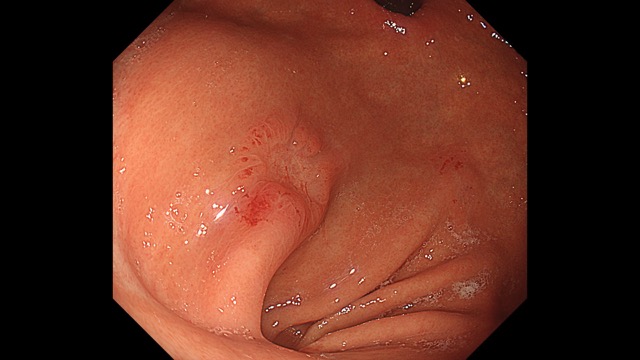

胃002